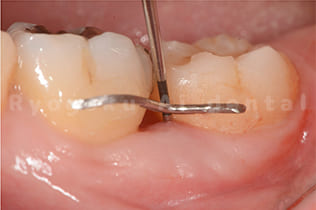

- ブラッシング指導と再度歯周ポケットの確認

- 衛生士と一緒に歯磨きの状態を確認します。

- 再度プローブにて歯周ポケットの状態を確認します